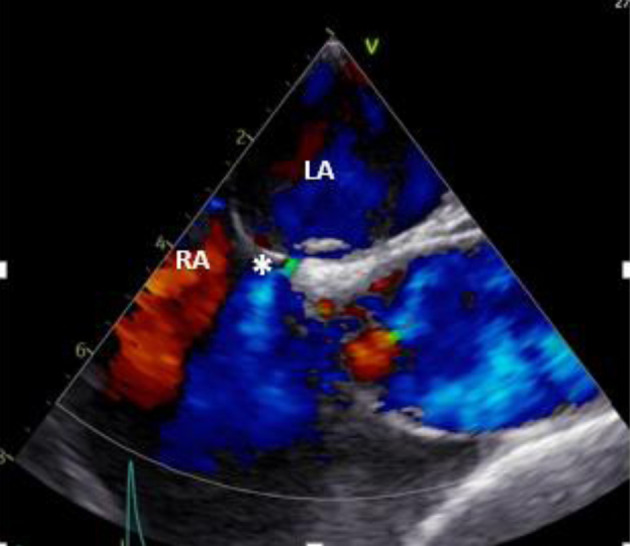

双房间隔(DIAS)现象是一种特别罕见的房间隔畸形亚型,其特点是存在双膜将心房分隔开来,形成一个独特的心房间隙。这种独特的解剖结构与矛盾性右向左分流有关,可能导致栓塞性缺血性脑卒中。在此背景下,我们报告了一例罕见病例,患者是一名 34 岁女性,突发短暂性脑缺血发作(TIA),被诊断为卵圆孔未闭(PFO)和邻近的一个小的房间隔缺损(ASD),并伴有 DIAS。经食道超声心动图和心脏磁共振成像(MRI)证实了这一诊断,并使用经导管封堵器成功治疗了该病。

The phenomenon of double interatrial septum (DIAS) represents a particularly rare subtype of atrial septal malformation, characterized by the presence of dual membranes separating the atria, resulting in a distinctive interatrial space. This unique anatomical structure has been linked to a paradoxical right-to-left shunt, potentially contributing to embolic ischemic strokes. Within this context, we report a rare case of a 34-year-old female who presented with a transient ischemic attack (TIA) and was diagnosed with patent foramen ovale (PFO) and a small adjacent atrial septal defect (ASD), along with the presence of a DIAS. The diagnosis was confirmed wit transoesophageal echocardiography and cardiac magnetic resonance imaging (MRI), and the condition was successfully treated with a transcatheter occluder device.